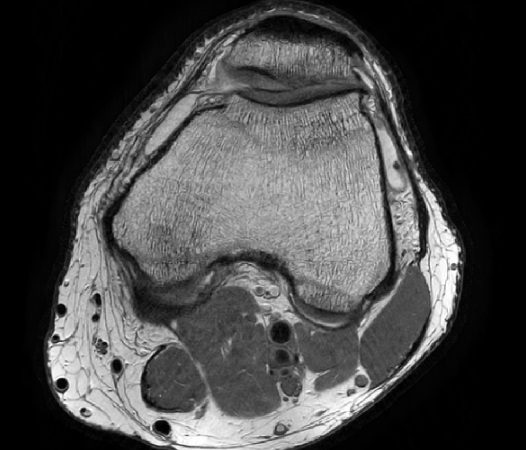

Compressed SENSE is the latest Philips MRI acceleration method, based on our industry leading dStream architecture. Compressed SENSE further expands the performance of dS SENSE, making MRI scans up to an additional 50% faster*, with virtually identical image quality. Alternatively, Compressed SENSE can increase the image resolution up to 40% within the same scan time. Compressed SENSE can be applied to all anatomies and works for both 3D as well as for 2D MRI acquisitions, making it a powerful asset for almost all clinical MRI exams.

Compressed SENSE is the Philips implementation of the compressed sensing principle. It combines dS SENSE, our industry leading parallel imaging method, with compressed sensing. As a result, it can reduce the scan times by up to 50% compared to current examinations without Compressed SENSE. Philips Compressed SENSE is unique for various reasons: